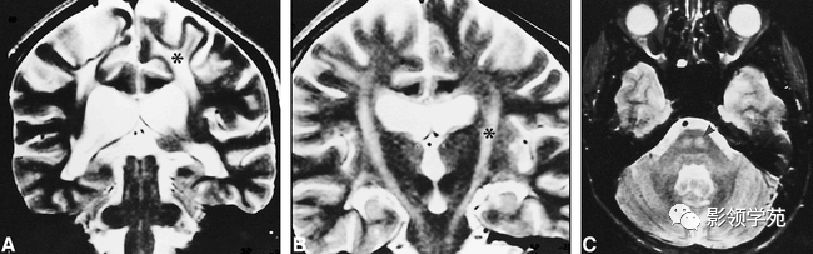

病因:缺乏芳香硫酸脂酶A,不能将硫酸脂分解成脑脂和无机硫,而沉积于少枝胶质细胞膜上,引起髓鞘形成障碍和广泛脱失。 影像:两侧大脑半球脑室周围及半卵圆中心脑白质长T1、长T2信号,形态不规则,无占位效应,无强化 。可累及内囊后肢和其它白质通路、小脑和脑干,伴弥漫性脑萎缩。但不累及皮层下下弓状纤维 。